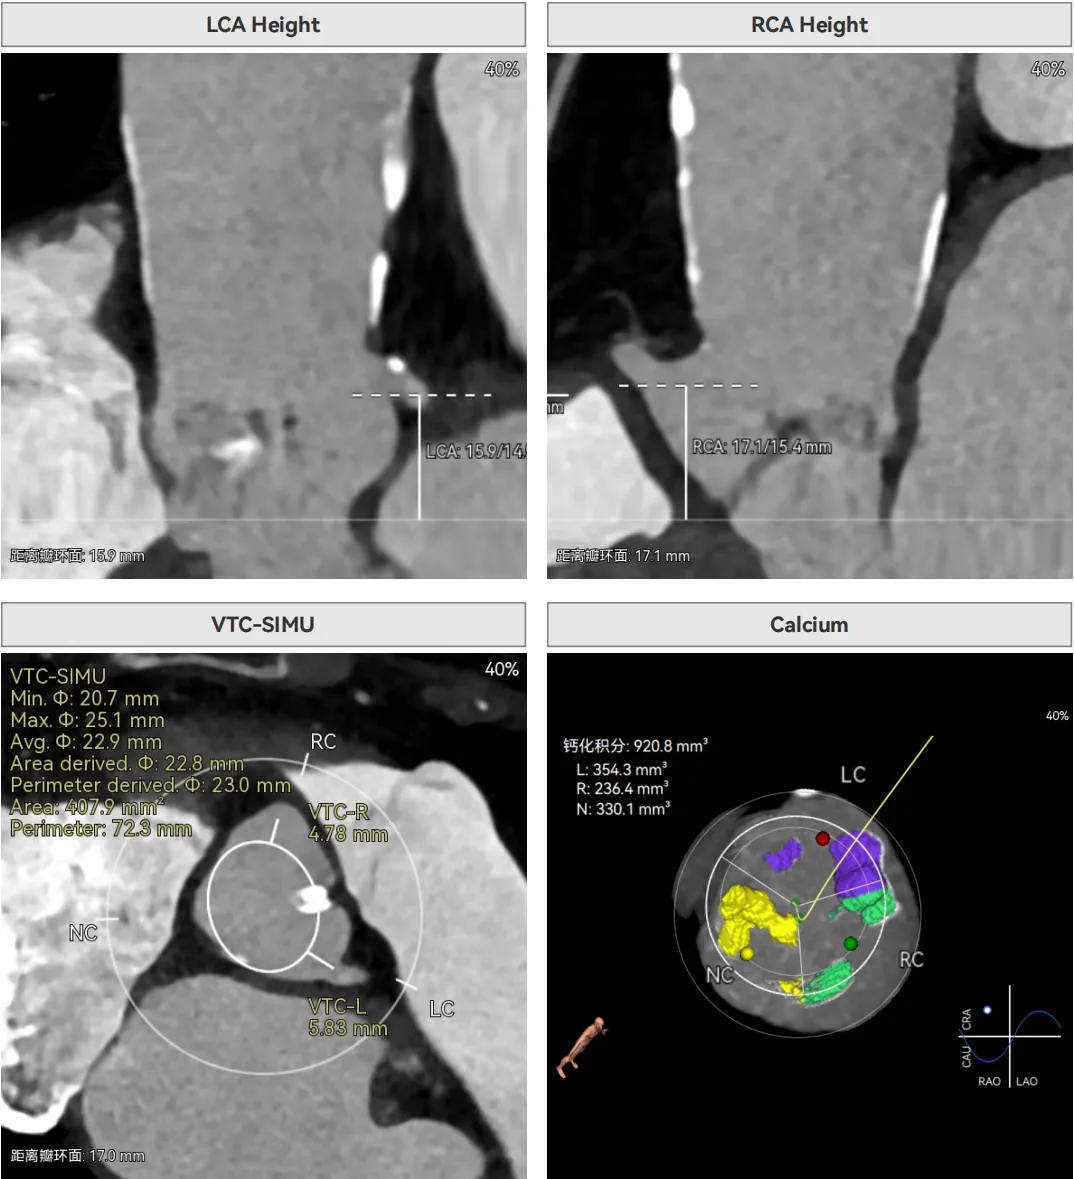

双侧冠脉开口高度可,VTC空间充足,无冠脉风险,双冠内多处钙化,术中评估冠脉支架植入必要性。

左室内径较小,但合并轻度反流,低循环崩溃风险,室间隔膜部长度<3mm,有一定术后起搏器植入风险。